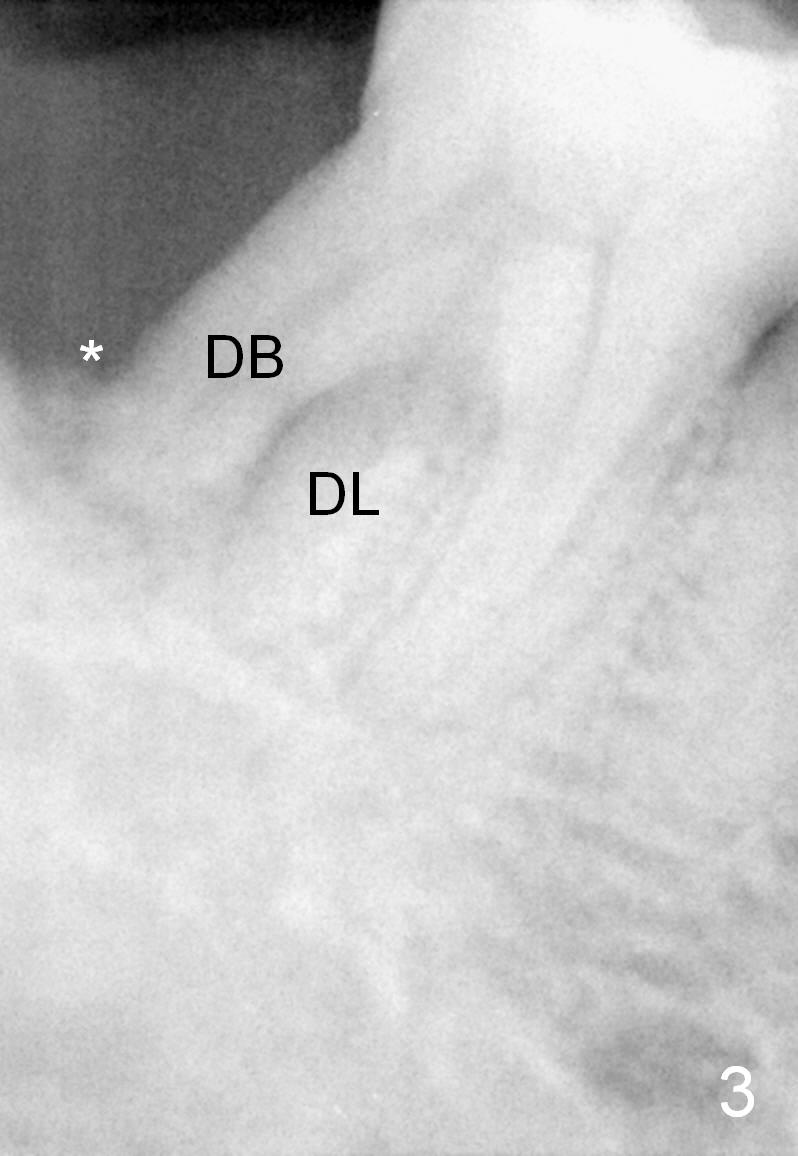

Fig.6 is an illustration after extraction (S: septum; M: mesial socket).  Osteotomy is initiated with a pilot drill in the distal aspect of the mesial socket or the mesial aspect of the septum (Fig.7).  The osteotomy is enlarged with osteotomes; at the same time the septum is being pushed distally (Fig.8 blue arrow) with leaning the osteotomes distally (white arrow).  When an implant is placed, the apex is mainly seated in the mesial socket, while the coronal end is more or less inclined distally for restoration.  The apical half of the distal sockets is packed with collagen plug or dressing, whereas the remaining sockets and coronal exposed threads are filled with bone graft (Fig.9,10 red circles).  An incision is made if needed for better visibility.   The most coronal socket is going to be obliterated by a cemented or healing abutment.  Does the treatment planning help surgery?